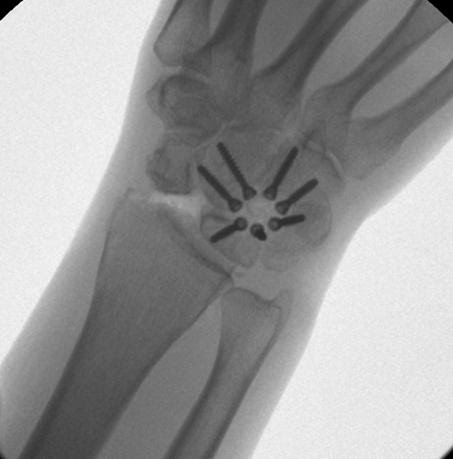

Aşağıda gösterildiği gibi, instabiliteyi sabitlemek için volar ve dorsal ligamanın skafolunatını tendon grefti ile yeniden yapılandırmak genellikle tercih edilen prosedürdür.